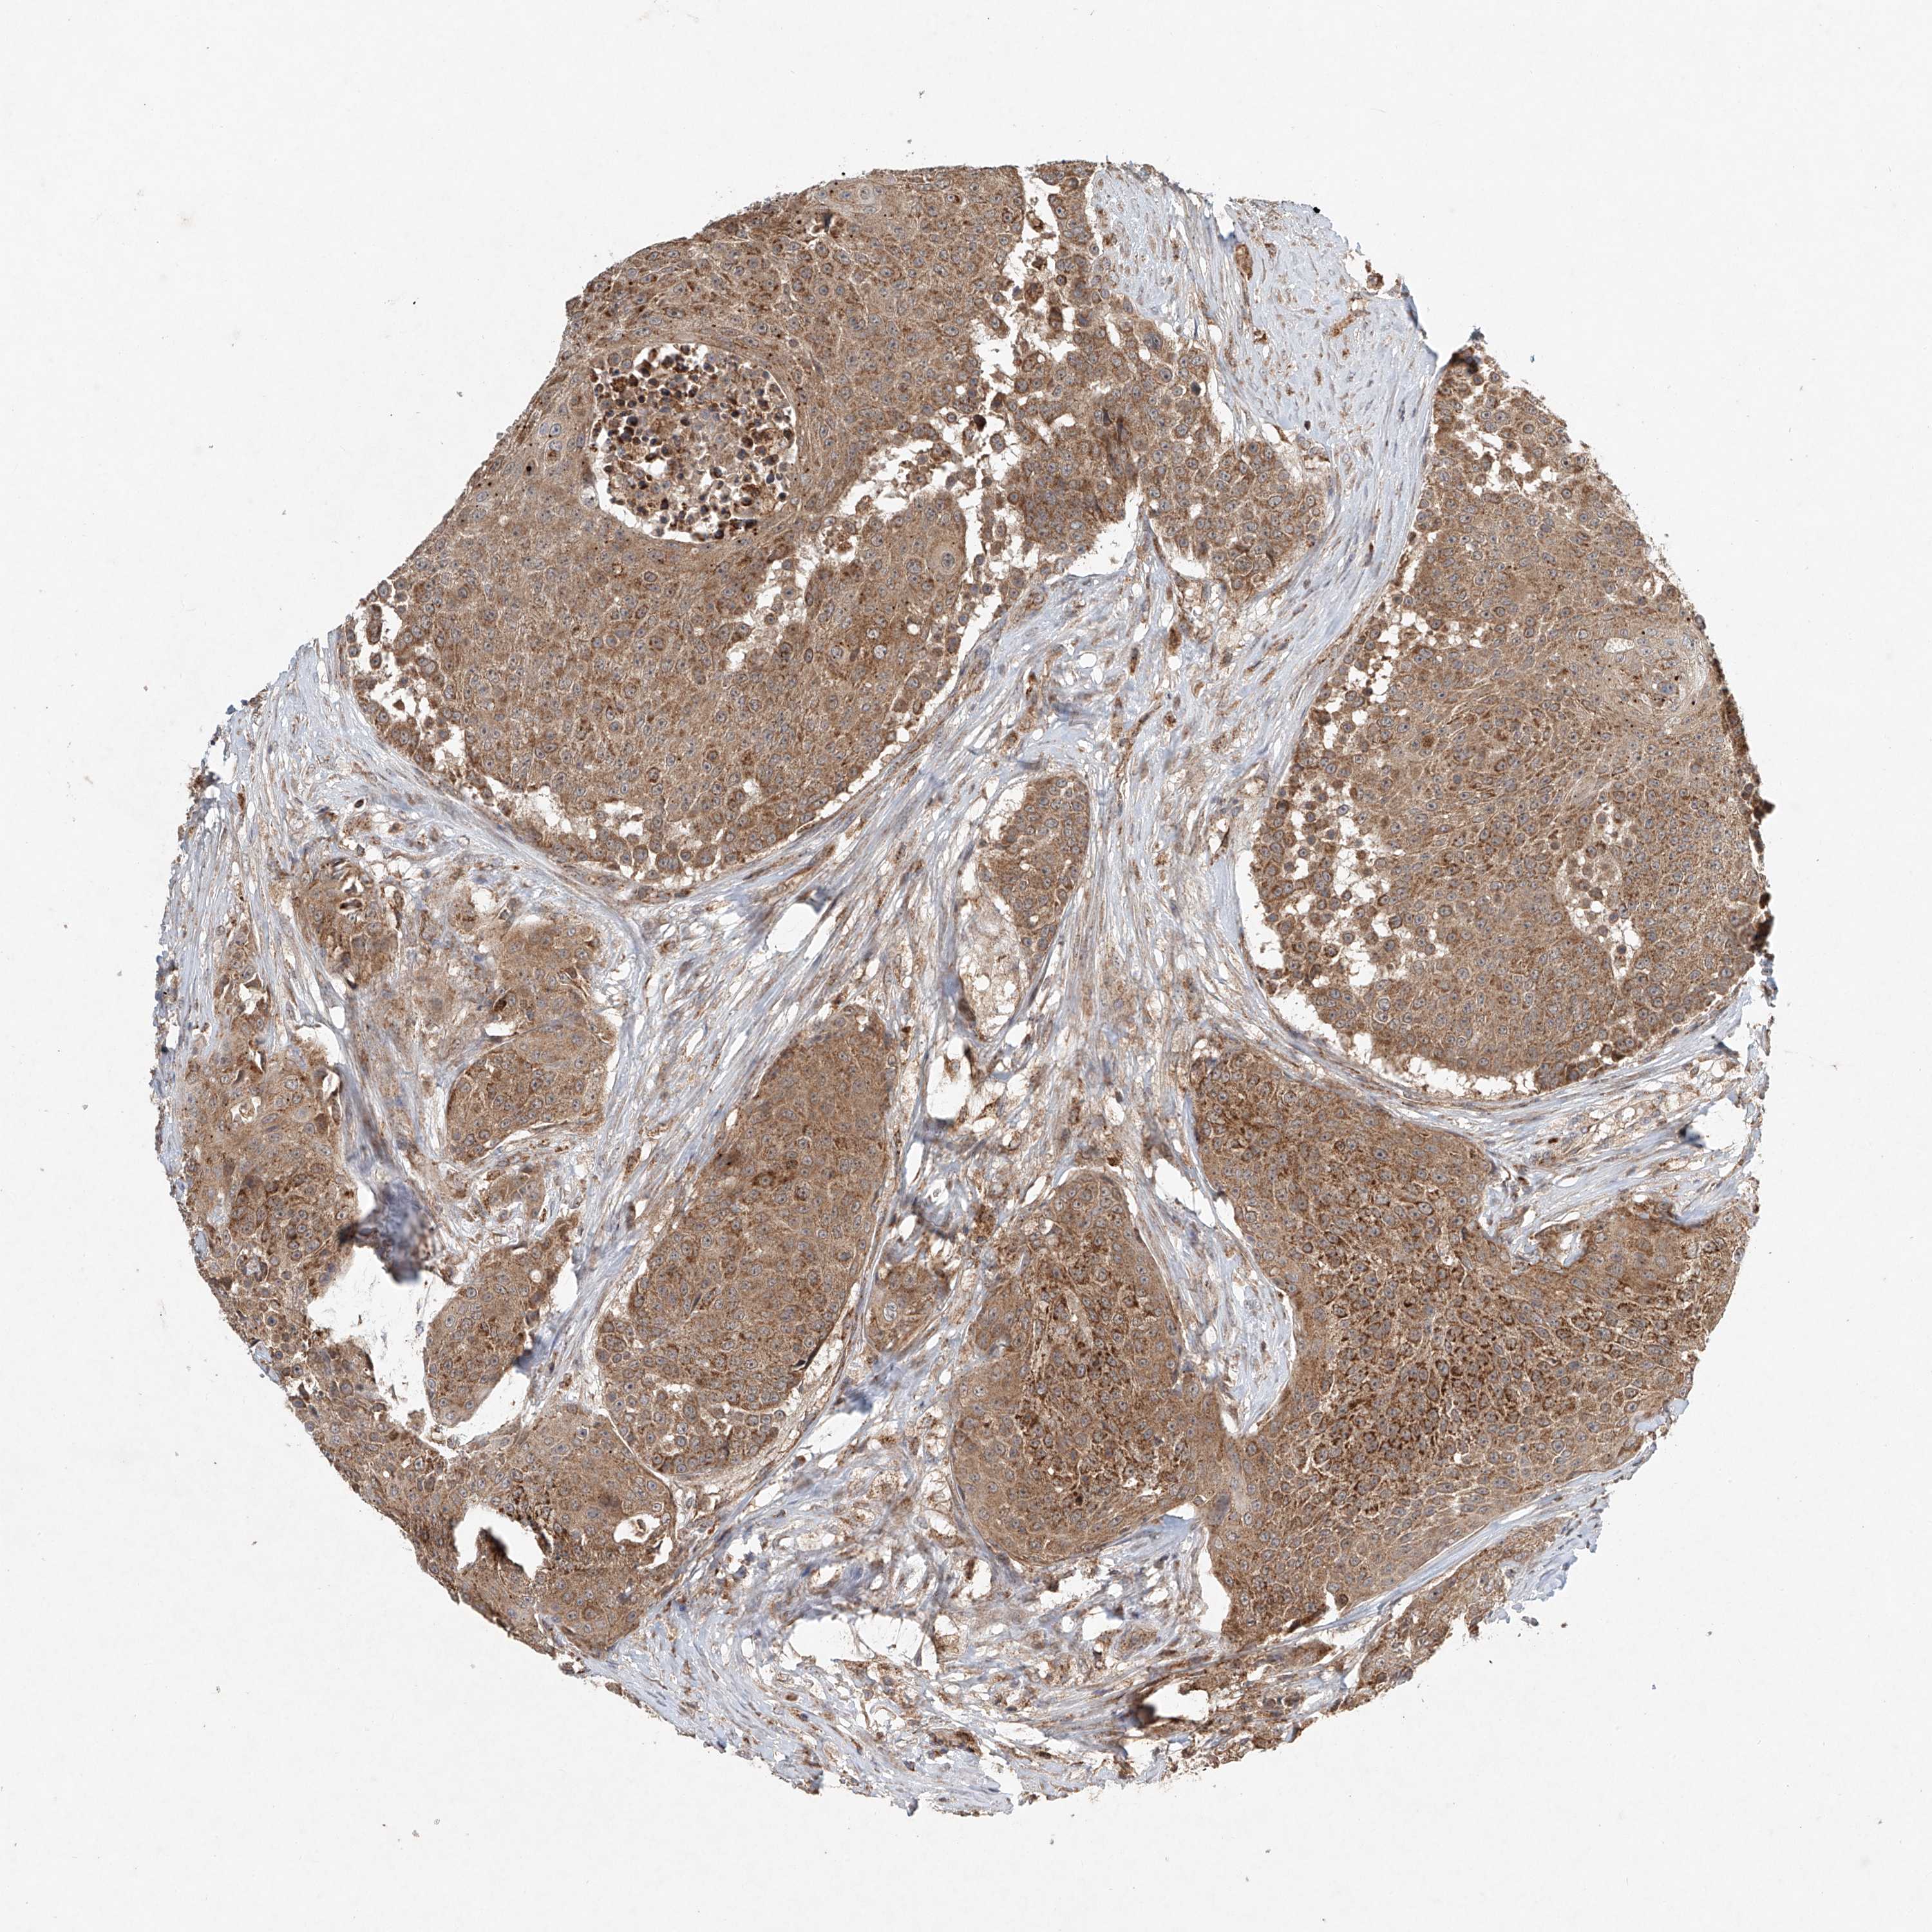

UROTHELIAL CANCER - Protein expressioni

A mouse-over function shows sample information and annotation data. Click on an image to view it in a full screen mode. Samples can be filtered based on level of antibody staining by selecting one or several of the following categories: high, medium, low and not detected. The assay and annotation is described here.

Note that samples used for immunohistochemistry by the Human Protein Atlas do not correspond to samples in the TCGA dataset.

Antibody stainingi

Antibody staining in the annotated cell types in the current human tissue is reported as not detected, low, medium, or high, based on conventional immunohistochemistry profiling in selected tissues. This score is based on the combination of the staining intensity and fraction of stained cells.

Each image is clickable and will lead to virtual microscopy that enables deeper exploration of all samples and also displays staining intensity scores, fraction scores and subcellular localization as well as patient and tissue information for each sample.

Antibody HPA031157

Staining

High

Medium

Low

Not detected

Intensity

Strong

Moderate

Weak

Negative

Quantity

>75%

75%-25%

<25%

None

Location

Nuclear

Cytoplasmic/membranous

Cytoplasmic/membranous,nuclear

Urothelial carcinoma, Low grade

Urothelial carcinoma, High grade